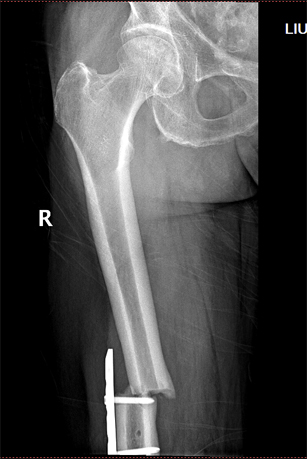

患者刘先生,2017年1月在外院行“右侧全膝关节置换术”,术后4个月不慎摔伤致右股骨髁上骨折,骨折移位,在我院关节外科-创伤骨科成功行骨折复位钢板内固定术,术后恢复良好。今年4月不慎再次摔伤,导致钢板近端骨折,骨折端成角、旋转移位。患者及家属出于对我院整体实力的信任,再次入住我院关节外科-创伤骨科。

术前影像

我院关节外科-创伤骨科副主任医师王兴龙通过详细查体及全面的影像学检查,综合评估病情后,发现貌似简单的骨折背后隐藏着复杂的情况。因为患者上次股骨髁上骨折后,股骨远端髓腔被增生骨痂封闭,且计划实施的髓内钉固定术,常规远端锁钉的位置骨质有缺损,如锁钉打入这一缺损区,固定将很不稳定,大大影响手术效果。如何使远端锁钉跨过缺损区,精准置入缺损两端健康骨质是此次手术的难点。如果以常规手术程序操作,将很难进行。我院关节外科-创伤骨科借助目前骨科领域先进的3D打印技术,完美地解决了这一问题。